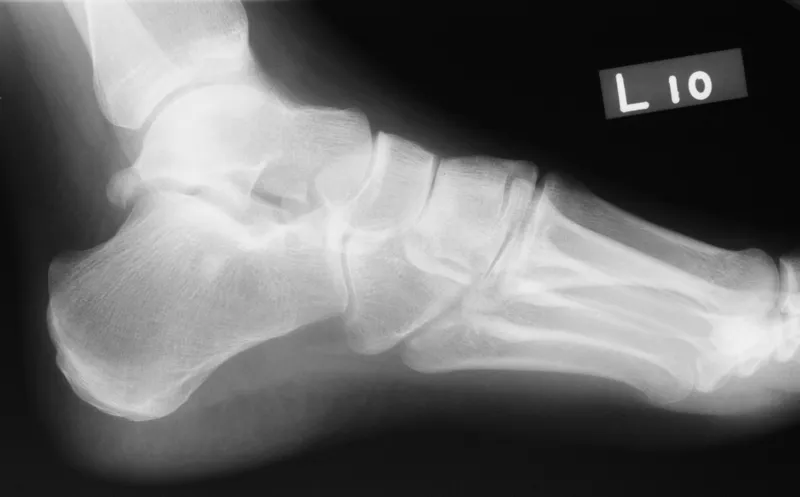

- Accessory Ossicles: Unfused centers; smooth, corticated.

- Foot/Ankle:

- Os Trigonum (post. talus; impingement).

- Os Naviculare (medial navicular; Type II pain).

- Os Peroneum (peroneus longus tendon).

- 📌 Mnemonic (Foot): "To New Places".

- Key: Variations = corticated; Fractures = non-corticated, sharp.